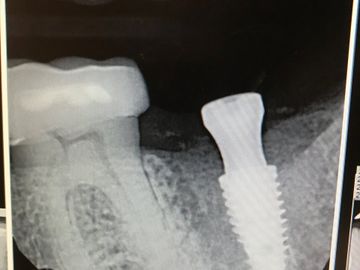

Send an X-ray to the LAB so they know where the implant is in relation to bone. This x-ray above shows the tussie measurement gauge finger tightened down on implant.

Was the implant placed Crestal or Subcrestal? The lab needs to know to create narrow emergence profile initially. Share an x-ray so lab can choose correct margin and design.

Most important: the margin of the abutment should be 1.5mm-2.0mm above the bone AND 1-2mm below the gingival margin on buccal